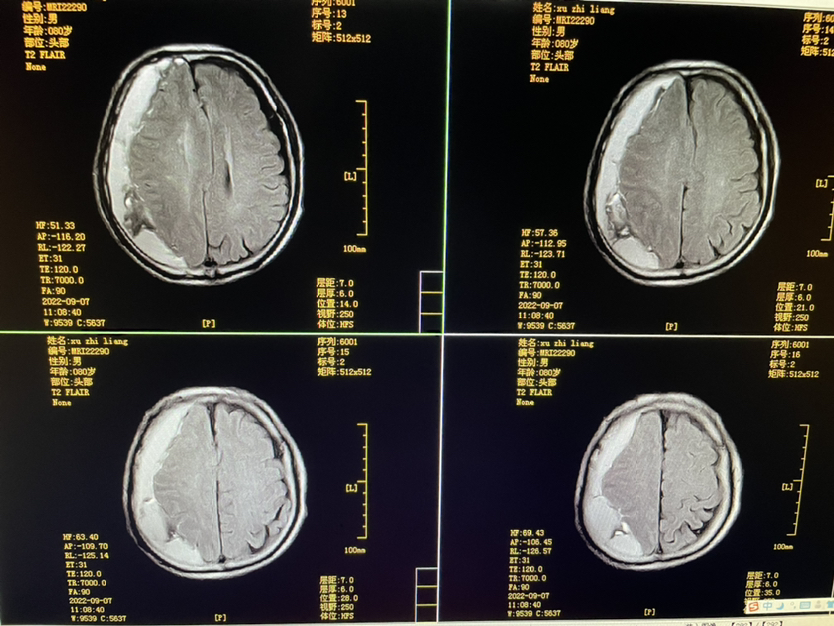

明确外伤史二月,80y,